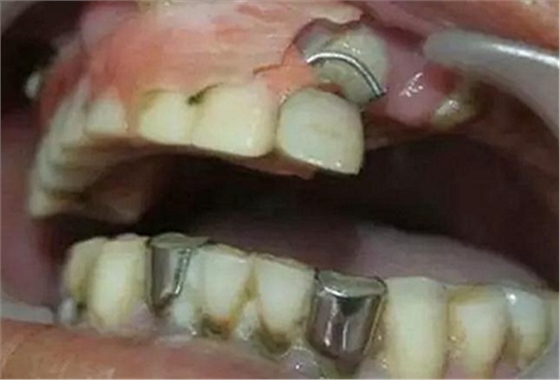

2、局部促進因素的檢查

檢查有無不良的義齒或固定冠、橋,有無鄰面充填體的懸突,或不良的正畸矯治器,修復(fù)材料的表面是否光潔,有無錯殆、不良習(xí)慣、食物嵌塞、解剖異常等(如畸形舌側(cè)溝、附著齦過窄、系帶附著異常等)。